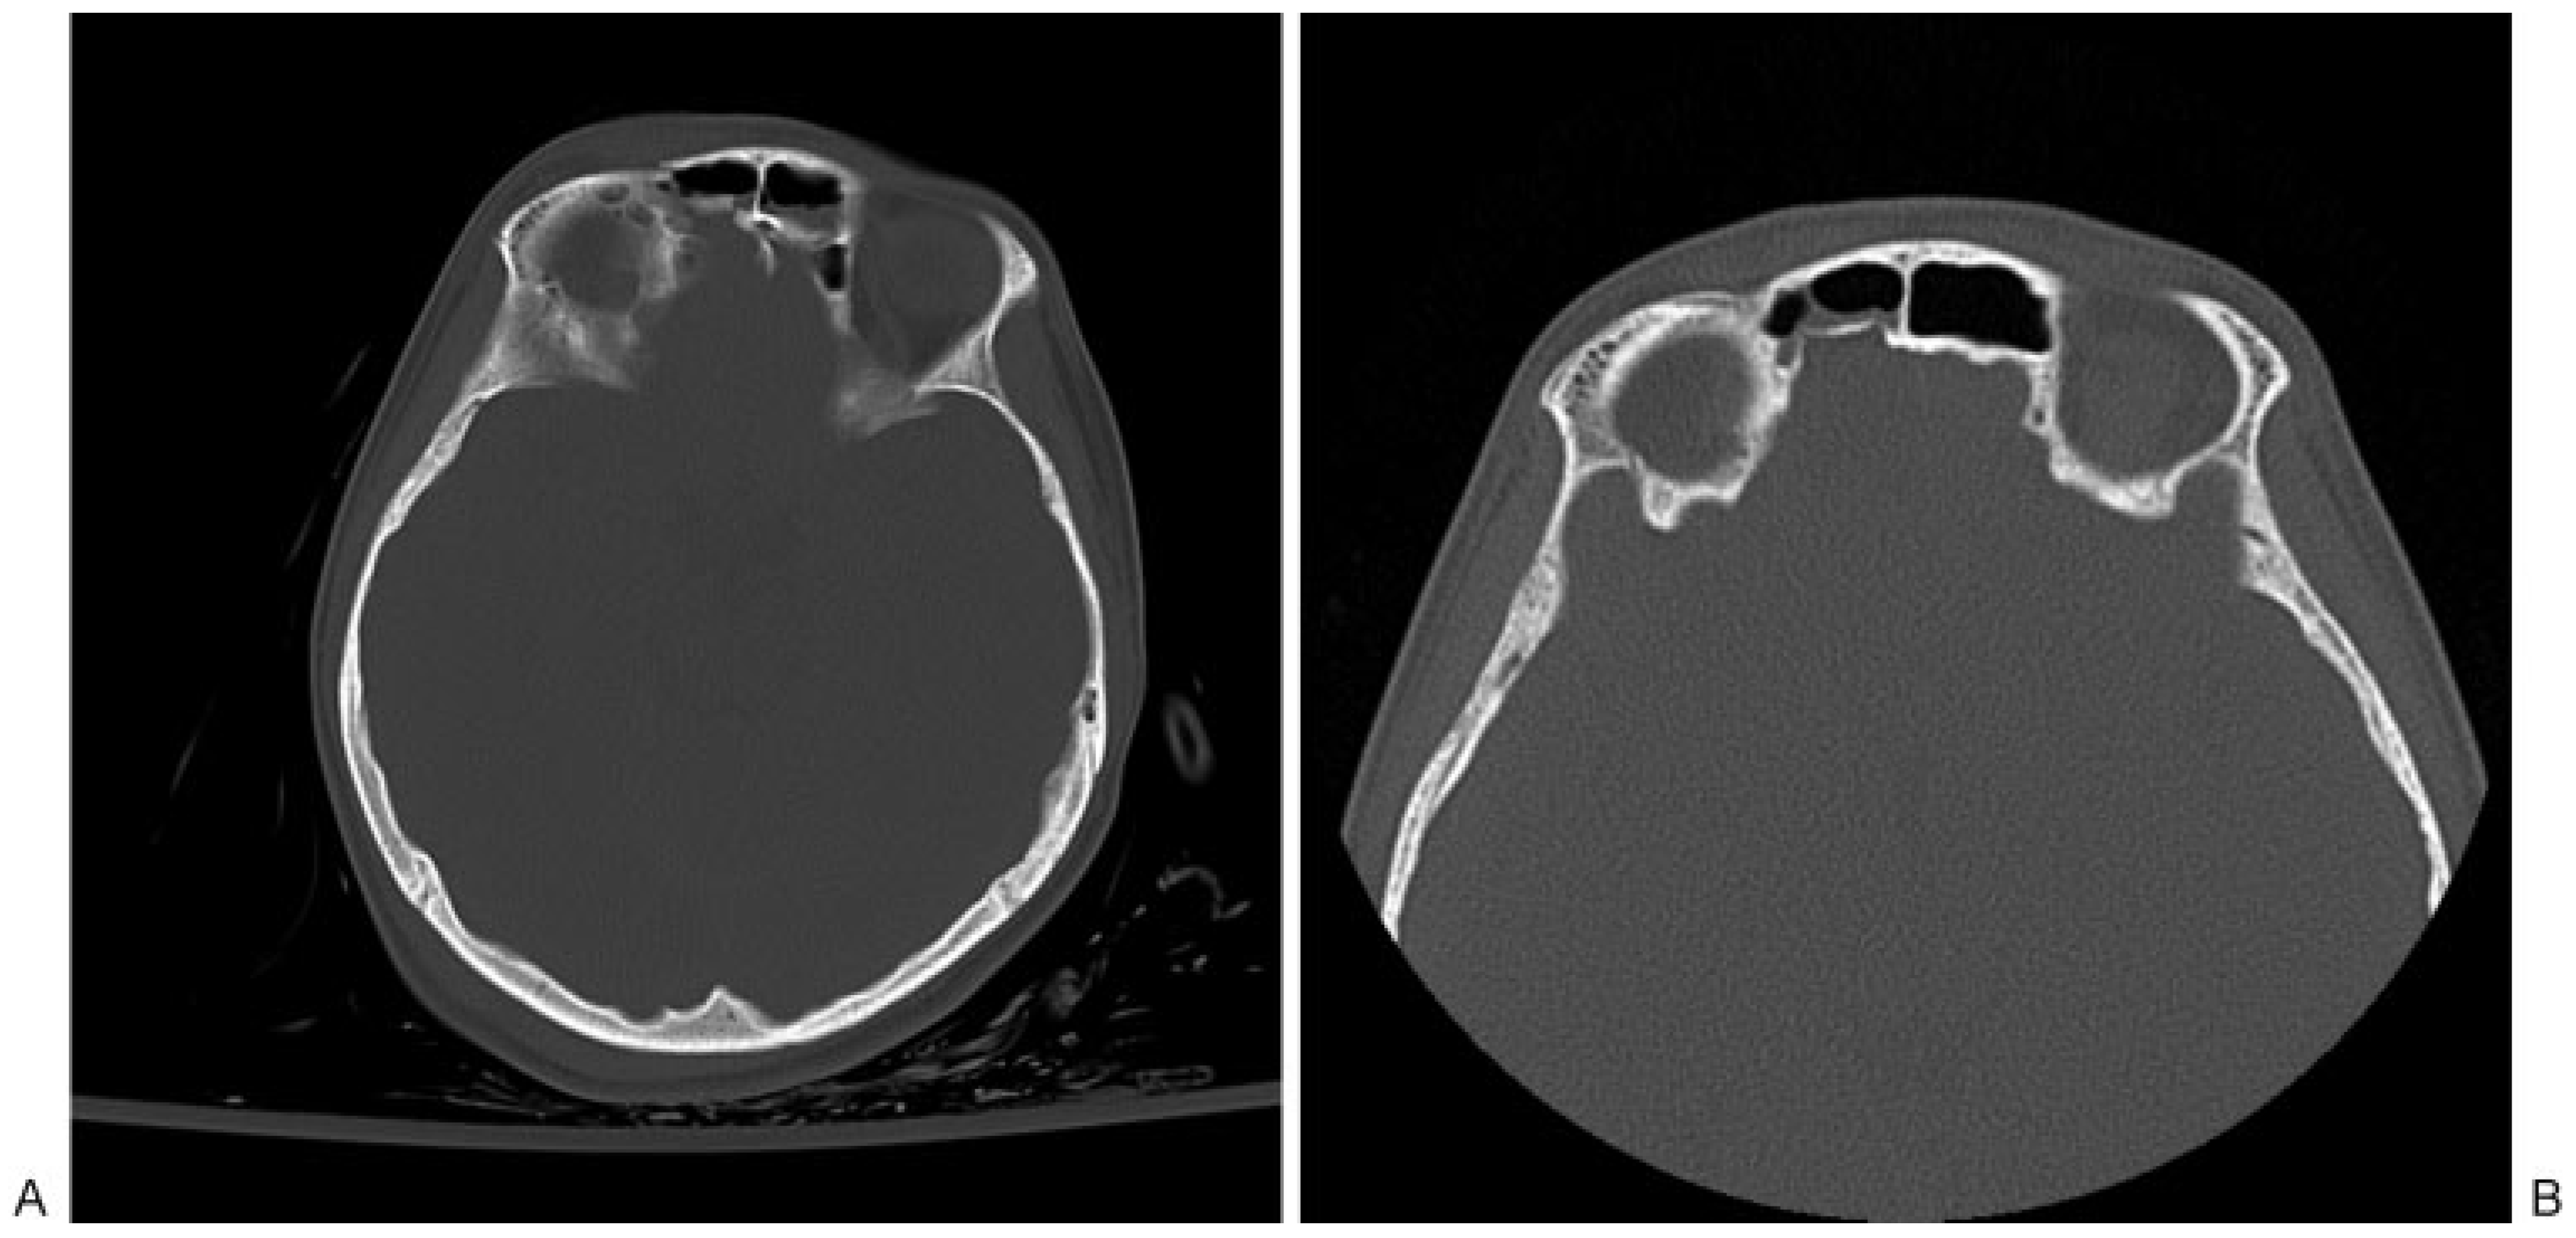

Anterior Table Fractures

Posterior Table Fractures

Nasofrontal Duct Injury